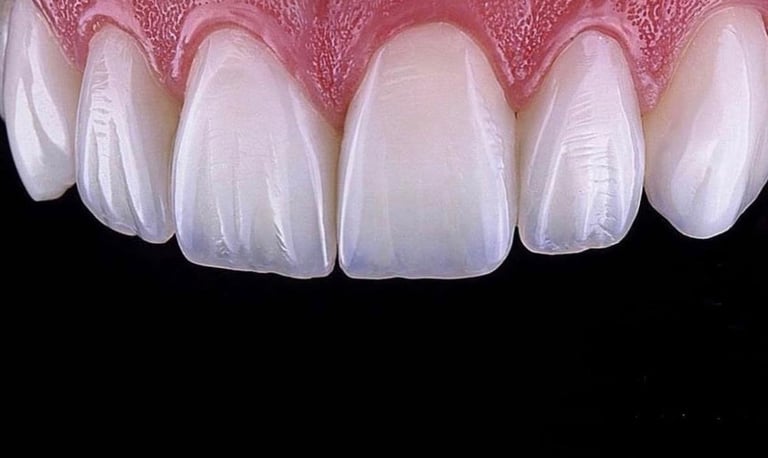

Veneers

Transform your smile with dental veneers—thin, custom-made layers that cover the front surface of your teeth.

At Dr. Teeth, we specialize in composite veneers and ceramic veneers, which are ideal for correcting:

Veneers provide a natural look, minimal invasiveness, and long-lasting aesthetics—perfect for anyone who wants a radiant Hollywood smile.